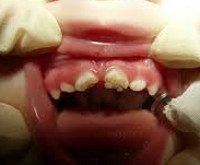

Стадия глубокого кариеса (30. 48 месяцев) - характеризуется поражением эмали и большей части дентина резцов верхней челюсти. Поражение моляров верхней челюсти достигает стадии среднего кариеса; клыков и вторых моляров верхней челюсти, а также первых моляров нижней челюсти - поверхностного кариеса. На данной стадии бутылочного кариеса ребенок страдает от зубной боли, плохо спит, отказывается от приема пищи. Стоматологическая помощь заключается в лечении глубокого кариеса, по показаниям - хирургическом или ортопедическом лечении.